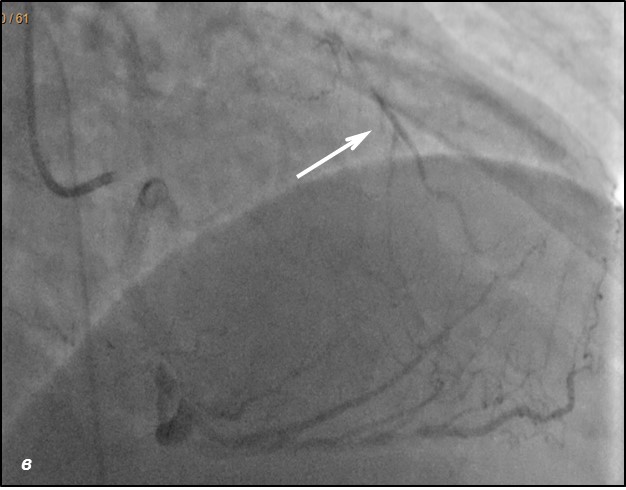

До проведения реваскуляризации миокарда пациент получал двойную антиагрегантную терапию (клопидогрел 75 мг, ацетилсалициловая кислота - 300 мг ежедневно). Чрескожное коронарное вмешательство было разделено на два этапа. Первым этапом – планировалось выполнить реканализацию и стентирование ПМЖВ, вторым – стентирование ПКА. Однако по данным повторной коронарографии было выявлено сужение тела ствола левой коронарной артерии (ЛКА) на 30%, окклюзия от устья передней межжелудочковой артерии (ПМЖВ), постокклюзионный сегмент заполнялся по слабым внутри- и межсистемным коллатералям, устьевое сужение огибающей артерии (ОВ) 60%, окклюзия средней трети правой коронарной артерии (ПКА), постокклюзионный сегмент заполнялся по внутрисистемным перетокам. Показатель Syntax Score для данного пациента составил 34.5. Учитывая, что по данным ранее выполненной коронарографии, правая коронарная артерия оставалась проходимой, а передняя межжелудочковая ветвь была окклюзирована и на момент реваскуляризации срок окклюзии составлял 7 лет, была проведена сменена тактики и первым этапом выполнена реканализация правой коронарной артерии, а спустя 2 суток – реканализация и стентирование передней межжелудочковой ветви от устья с баллонной ангиопластикой огибающей ветви (рис.1,2). Учитывая, что проводилась реканализация хронической окклюзии, в обе коронарные артерии были имплантированы стенты с лекарственным покрытием Resolute ONYX (Medtronic).

Рис.1 Ангиограмма правой корнарной артерии. а) при коронарографии правой коронарной артерии –артерия окклюзирована от уровня п/3 (стрелка); б) проходимость по правой коронарной артерии полностью восстановлена; в) после выполненной реканализации и стентирования ПКА отмечаются межсистемные перетоки в ПМЖВ-ЛКА (стрелка)

Рис.2 Ангиограмма левой коронарной артерии. а) при коронарографии левой коронарной артерии –артерия окклюзирована от устья (стрелка); б) проходимость по левой коронарной артерии полностью восстановлена